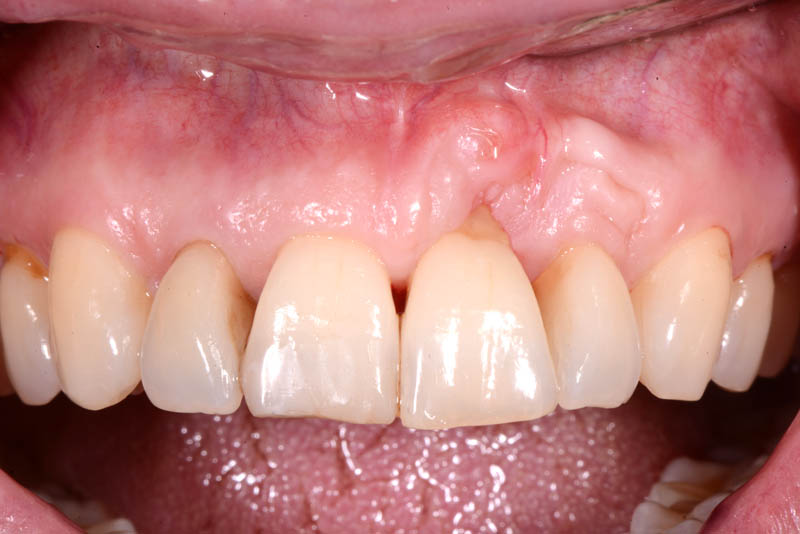

The rehabilitation of this periodontally compromised tooth required a multidisciplinary approach, combining both periodontal and orthodontic treatments.

Following an initial phase of non-surgical periodontal therapy aimed at removing subgingival calculus, Dr. Anna Mariniello performed both upper and lower alignment using a lingual, non-bracket orthodontic technique, employing active retainers applied to the lingual surfaces of the teeth.

At the end of the orthodontic treatment, a coronally advanced flap was performed according to the De Sanctis and Zucchelli technique, involving papilla preservation and connective tissue grafting, to restore the gingival contour and the papilla between teeth 21 and 22.

The healing has now reached a 5-year follow-up.